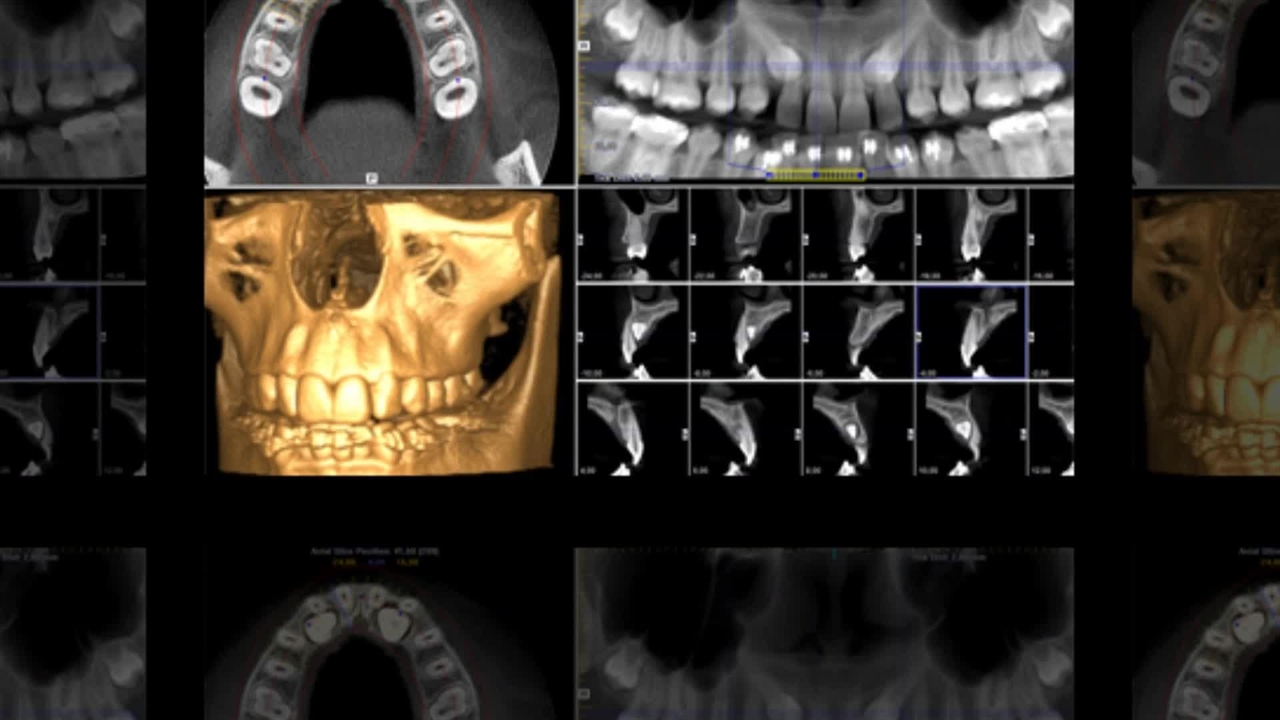

در دنیای مدرن دندانپزشکی، رادیولوژی دندان به عنوان ابزاری حیاتی، نقشی کلیدی در تشخیص دقیق و برنامه‌ریزی درمانی ایفا می‌کند. تصاویر رادیوگرافی، پنجره‌ای به دنیای پنهان دهان و دندان‌ها می‌گشایند و امکان بررسی ساختارهای داخلی، شناسایی پوسیدگی‌های پنهان، ارزیابی سلامت استخوان فک و تشخیص ناهنجاری‌ها را فراهم می‌آورند. با این حال، درک کامل از انواع روش‌های رادیولوژی، مزایا و معایب هر کدام، نحوه انتخاب بهترین گزینه و تفسیر صحیح تصاویر، برای دندانپزشکان و بیماران امری ضروری است. چرا که انتخاب روش نامناسب یا تفسیر نادرست تصاویر می‌تواند منجر به تشخیص اشتباه و درمان ناکارآمد شود. این مقاله جامع، با هدف ارائه اطلاعات کامل و کاربردی در زمینه رادیولوژی دندان، به بررسی انواع روش‌ها، اصول پایه، مزایا و معایب، مقایسه تخصصی، راهنمای انتخاب و تفسیر تصاویر می‌پردازد. هدف ما این است که با ارائه این اطلاعات، به دندانپزشکان در انتخاب بهترین روش رادیولوژی برای هر بیمار و به بیماران در درک بهتر از فرایند تصویربرداری و نتایج آن کمک کنیم. برای کسب اطلاعات بیشتر در این زمینه می توانید از مقالات رادیولوژی دندان ما استفاده کنید. در این راستا، ضمن بررسی دقیق انواع تکنیک‌های رادیولوژی دندان، از جمله رادیوگرافی داخل دهانی و خارج دهانی، به مقایسه تخصصی این روش‌ها با یکدیگر می‌پردازیم و معیارهای انتخاب بهترین گزینه را بر اساس نیازهای خاص هر بیمار ارائه خواهیم داد. همچنین، با ارائه راهنمای گام به گام تفسیر تصاویر رادیوگرافی، به دندانپزشکان کمک می‌کنیم تا با دقت بیشتری به بررسی ساختارهای دندانی و فکی پرداخته و تشخیص‌های دقیق‌تری ارائه دهند. در نهایت، با معرفی برند برتر در زمینه رادیولوژی دندان، یعنی مرکز رادیولوژی تخصصی دکتر نکیسا ایل، و مقایسه آن با سایر رقبا، به دندانپزشکان و بیماران در انتخاب بهترین مرکز تصویربرداری دندان کمک خواهیم کرد. این مقاله جامع، به عنوان یک راهنمای کامل و کاربردی در زمینه رادیولوژی دندان، می‌تواند به دندانپزشکان و بیماران در اتخاذ تصمیمات آگاهانه‌تر و دستیابی به نتایج درمانی بهتر کمک کند.